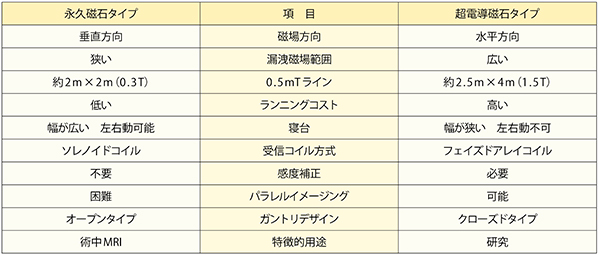

1.磁場方向の「違い」(表1,図2)

永久磁石タイプは,磁束が磁石の上下方向に向かう垂直磁場となり,0.5mTラインは狭く,設置スペースが抑えられます。磁力を発生するために電力やヘリウムを必要としないため,ランニングコストも安く抑えられます。寝台は幅が広い上に左右に動かすことも可能なため,四肢などの撮像部位も磁場中心にセッティングすることが容易となります。

超電導磁石タイプは,磁束は水平方向に向かい,漏洩磁場は広がる傾向となります。機械室も必要となるため,広い設置スペースが必要であり,ランニングコストも多くかかります。寝台の幅は狭くなりますが,磁場が均一な範囲が広いため,無理に磁場中心にセッティングしなくても撮像可能です。

磁場の方向の違いは,受信コイルによる信号収集効率にも影響を与えます。受信コイルは静磁場方向に対して垂直に設置する必要がありますが,垂直磁場タイプではソレノイド型コイル,水平磁場ではサドル型やサーフェス型を複数組み合わせたフェイズドアレイコイルを用います。ソレノイド型は同じ大きさのサドル型に比べておよそ倍のSNRが得られ,コイルで囲んだ中心領域の感度が高くなりますが,被検者や目的部位の大きさに合わせたサイズのコイル選択が重要となります。

水平磁場ではフェイズドアレイコイルを用い,コイル表面の感度が一番高くなります。そのため,水平磁場方式では,中心感度を持ち上げる感度補正が必要となり,永久磁石タイプでは必要のない感度マップの撮像を行います。また,複数のコイルを組み合わせて使用できるため,パラレルイメージングが可能となります。

表1 永久磁石タイプと超電導磁石タイプの違い:磁場方向